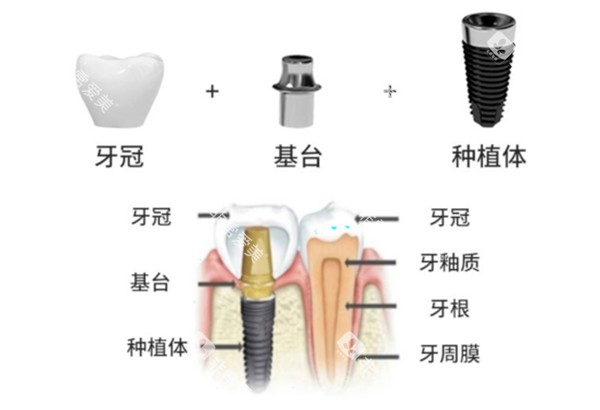

例如高岩石医生,作为优诺口腔哈尔滨地区的技术总监,擅长小创口智能化口腔种植技术、即刻种植技术等多种高难度种植技术;

医院配备了科技智能智能化的诊疗设备,能够为患者提供更更准一些、较高的效率的口腔诊疗服务。

无论是牙齿种植时的更准一些定位,还是正畸过程中的方案设计,较高的设备都能发挥重要作用。

以种植牙和正畸为例,有患者分享,在做诺贝尔种植牙手术时,护士会安慰紧张的患者,医生手法稳,手术时间短,术后修复快,第二天就能正常吃饭;正畸患者也表示,医生会制定详细的方案,复诊时耐心调钢丝,还会教导正确的刷牙方法。

种植牙患者做完手术后,牙齿稳固,吃东西不再有问题;